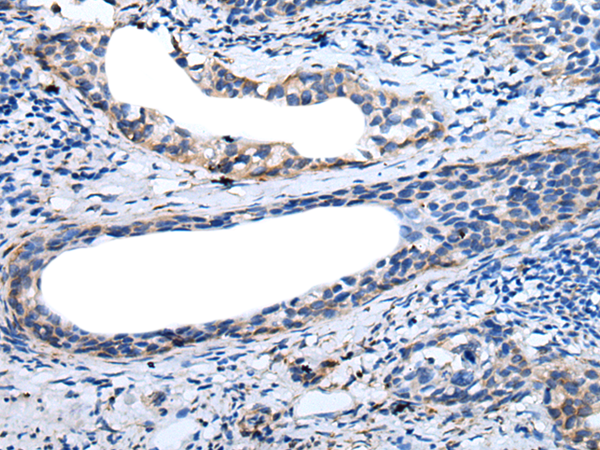

分类: 科研抗体货号: P12741别名: MTLRP应用: IHC反应种属: Human, Mouse, Rat